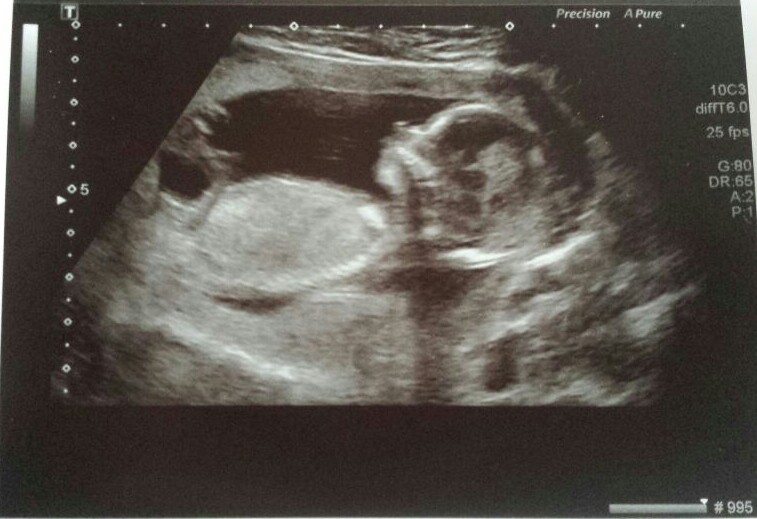

I am slowly starting to regret not finding out the gender of our baby at my last ultrasound scan and now it's driving me up the wall waiting....and waiting!

I would really appreciate any guesses as to whether my baby is a boy or a girl!